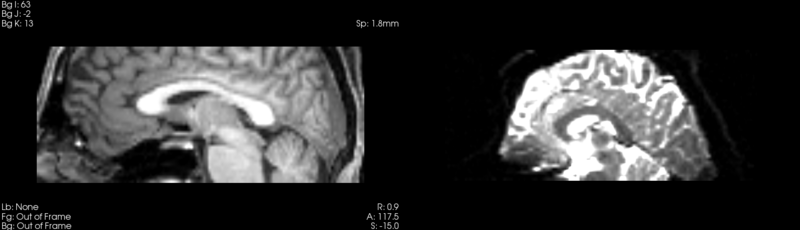

Registration of t1 weighted image to DTI space via a Diffeomorphic Demons registration.

current15:12, 4 May 2009Thumbnail for version as of 15:12, 4 May 20091,480 × 425 (204 KB)Rauscha (talk | contribs)Registration of t1 weighted image to DTI space via a Diffeomorphic Demons registration.